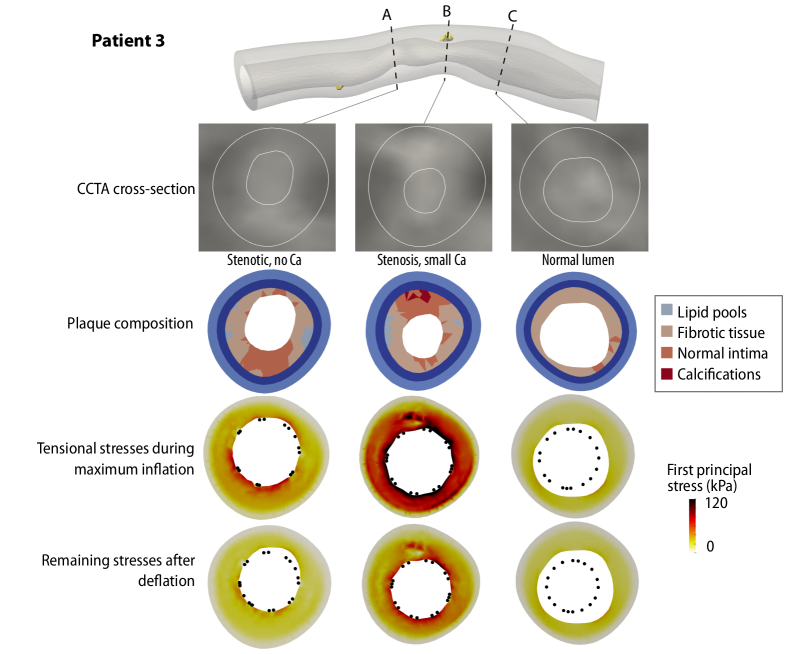

In the following, we present the complete results for the stress distributions in cross-sectional slices of the four numerical examples.

Refer to caption

Figure 17: First principal stress values in selected cross-sections during and after PCI; Patient 3. The plaque morphology is shown in the CCTA cross-sections and in the model. The stent cross-section is shown as black dots. Ca: Calcification.

Patient 3 shows no significant calcifications; the lesion mainly comprises fibrous tissue. We observe the highest stresses during the maximum balloon inflation in the location of the most severe stenosis. However, the remaining stresses after the balloon withdrawal are reduced drastically and more evenly distributed in the tissue than in the lesions with calcifications.